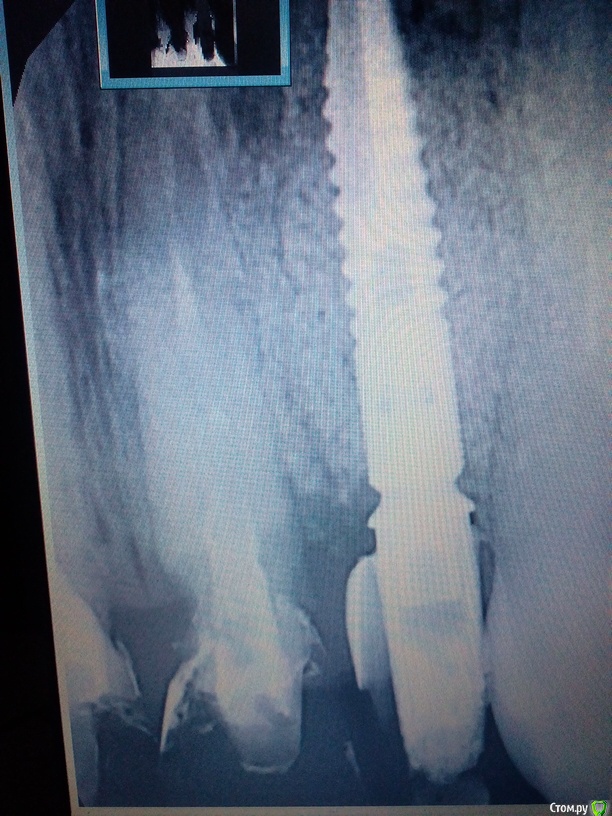

Bier Опубликовано 21 октября, 2015 Поделиться Опубликовано 21 октября, 2015 мягкие ткани туда нужно подсаживать как минимум и надо rg, где там имплантат смотреть. Ссылка на комментарий

victor57 Опубликовано 23 октября, 2015 Автор Поделиться Опубликовано 23 октября, 2015 (изменено) Вот снимок.расстояние оптимальное на мой взгляд. Изменено 23 октября, 2015 пользователем victor57 Ссылка на комментарий

Bier Опубликовано 23 октября, 2015 Поделиться Опубликовано 23 октября, 2015 Там нет места для мягких тканей, Дмитрий прав Ссылка на комментарий

Дмитрий Никитюк Опубликовано 23 октября, 2015 Поделиться Опубликовано 23 октября, 2015 Вот снимок.расстояние оптимальное на мой взгляд.Странная проекция снимка. Складывается впечатление, что имплантат стоит вплотную к клыку. Или так и есть? Если да, то тогда нужно поработать с профилем времянки. Ссылка на комментарий